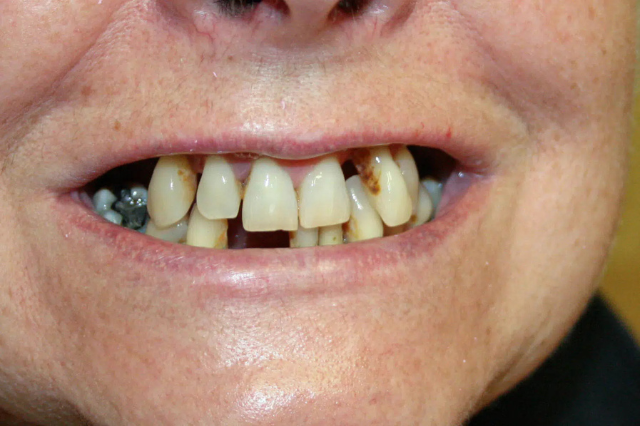

Teljes felső implantációs fogpótlás

Az utóbbi 2-3 évben kezdtek tünetek jelentkezni ezeket első körben konzervatív módon a gyökérkezelés felfrissítésével, majd később a fogak rezekálásával próbáltuk kezelni.

A tervezés során felmerült a felső régióban megmaradt összesen 2-2 darab saját fog eltávolításának lehetősége, de páciensünk nagyon ragaszkodott ezek megtartásához.